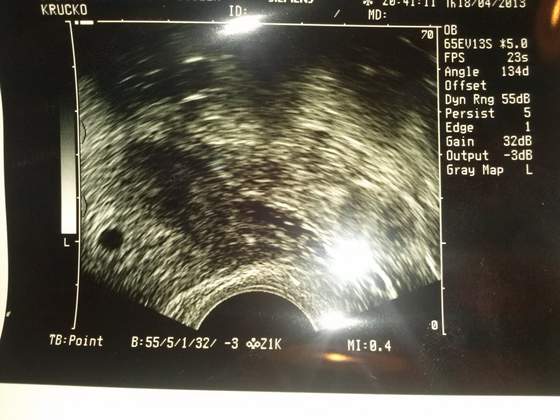

W międzyczasie bóle ustały bo nafaszerowałam się nospą... Ciąży brak, już na 300%, USG nie wskazało, żadnych zmian, jajniki prawidłowe, endometrium też, zero zmian. Morfologia też w porządku. Skąd więc ten ból? Niebardzo potrafili mi pomóc... Jedyne co to przy badaniu na fotelu ginekologicznym doktorowa wyczuła jakieś małe guzki w zatoce Douglasa, wskazujące na prawdopodobną endometriozę. Zaleciła zgłębienie tego tematu u ginekologa.... Mój Gin już kiedyś podejrzewał to u mnie, stąd te możliwe bólu, zwłaszcza w czasie okresu...A byłam pewna, że bóle to torbiel...